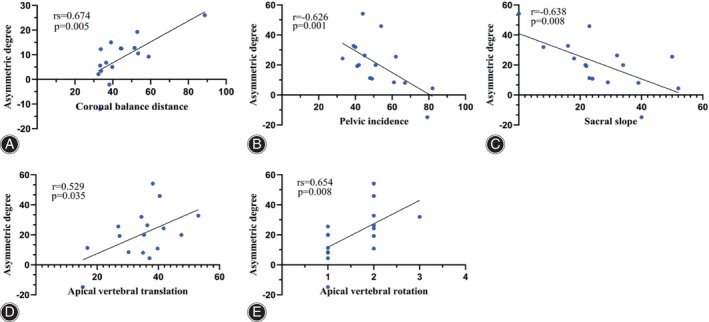

The asymmetric degree (AD) in the change of the multifidus was significantly higher at the apex of both the main and fractional curves compared to the erector spinae (Z = ‐4.839, p < 0.05; Z = ‐2.695, p < 0.05). The change in AD of the erector spinae was weakly positively correlated with the AVR (0 < rs <1, p < 0.05), while that of MS was weakly negatively correlated with TLK in Type A (−1 < rs <0, p < 0.05) (Fig. 4). The change in AD of the erector spinae was strongly positively correlated with CBD at the apex of the main curve in Type B (0 < r < 1, p < 0.05) (Fig. 5). At the apex of the fractional curve, the change in AD of the erector spinae was strongly positively correlated with CBD (0 < rs <1, p < 0.05), and the change in AD of the multifidus was strongly positively correlated with AVR (0 < rs <1, p < 0.05), while it was strongly negatively correlated with PI and SS (−1 < r < 0, p < 0.05) in Type C (Fig. 6).

Our analysis of the results revealed patients in Type B and C demonstrated higher fat infiltration in MS on the concave side of both the main and fractional curves when compared to those in Type A. The asymmetric degree of ES change was positively correlated with CBD at the main curve in Type B and at the fractional curve in Type C, and that of MS was positively correlated with AVR, while negatively strong‐correlated with PI and SS in Type C.

It is noteworthy that in our study, the extent of asymmetry in ES change exhibited a strong positive correlation with the CBD in Type B and C. Furthermore, the asymmetry in fatty infiltration within the multifidus muscle exceeded that of the erector spinae in all three subgroups. Reduced density of paraspinal muscles is identified as a contributor to coronal imbalance.ref. os14185-bib-0023 We posit that the relationship between the erector spinae and coronal spine stability becomes more pronounced following multifidus decompensation.

A prior study has established that the primary function of the multifidus muscle is to maintain the posterior sagittal rotational balance of the lumbar vertebrae.ref. os14185-bib-0030 In our current investigation, we observed a strong positive correlation between the degree of asymmetry in multifidus muscle changes and the AVR. Notably, there exists a negative correlation between qualitative muscle changes caused by fat infiltration and muscle strength.ref. os14185-bib-0036 The unopposed action of the deep spinal transverse and rotator muscles is a significant factor in initiating deformities in many idiopathic curves.ref. os14185-bib-0037 We hypothesize that this mechanism also operates in DLS. Conversely, this asymmetry showed a strong negative correlation with the PI and SS in Type C. Paravertebral muscles attach to the sacrum as they pass between the lumbar vertebrae and ilium. It seems reasonable that the larger the size of the multifidus, the greater the strength, and thus the greater the PI and SS angle. As is well known, there exists a negative correlation between qualitative muscle changes caused by fat infiltration and muscle strength. Because of the negative correlation between fat infiltration and muscle strength, the correlation between the multifidus fat infiltration and PI or LL is logical. Minetama et al. and Menezes‐Reis et al.ref. os14185-bib-0011, ref. os14185-bib-0012 identified that multifidus volume was positively correlated with PI and SS (I = 0.22; 0.08), and its fat infiltration was negatively correlated with PI (I = −0.11) in asymptomatic adults, in line with our findings. While they also found multifidus fat infiltration was positively correlated with SS (r = 0.15). The cause of the discrepancy with our results might be interpreted by the different diseases and study design. We believe that, in addition to coronal imbalance, these pelvic parameters can exacerbate paravertebral muscle degeneration.

It is not surprising that the degree of asymmetry in multifidus muscle changes positively correlated moderately with AVT in Type C, while the degree of asymmetry in erector spinae changes weakly correlated positively with AVR in Type A, as lateral vertebral translation often deviates from the concave side, and the unopposed action of deep spinal transverse and rotator muscles plays a significant role in these processes. Current guidelines stress the importance of addressing sagittal imbalance, but it is equally crucial not to disregard the coronal component. In our study, we observed that 26.2% of DLS patients displayed pre‐operative coronal imbalance among the 84 patients in our sample, which aligns with previous findings.ref. os14185-bib-0023, ref. os14185-bib-0038 Based on the CBD, we categorized patients as having either coronal balance (CBD < 3 cm) or coronal imbalance (CBD > 3 cm).ref. os14185-bib-0023, ref. os14185-bib-0039 In this investigation, Type B and Type C exhibited significantly greater CBD compared to Type A. Moreover, the asymmetrical degeneration of paraspinal muscles is linked to spine instability and may contribute to the progression of scoliosis.ref. os14185-bib-0006 Conversely, spinal deformity may also play a role in the development of fat infiltration in paraspinal muscles.